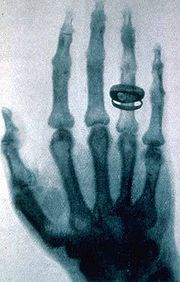

Вильгельм Конрад Рентген (1845 — 1923) — немецкий физик, первый лауреат Нобелевской премии по физике (1901). Он изучил и описал основные свойства ранее неизвестного излучения, которое получило название — рентгеновское. Как оказалось, икс-излучение способно проникать сквозь многие непрозрачные материалы; при этом оно не отражается и не преломляется. Рентгеновское излучение ионизирует окружающий воздух и засвечивает фото-пластины. Также Рентгеном были сделаны первые снимки с помощью рентгеновского излучения.

Рентгеновский снимок руки Альберта фон Кёликера, сделанный Рентгеном